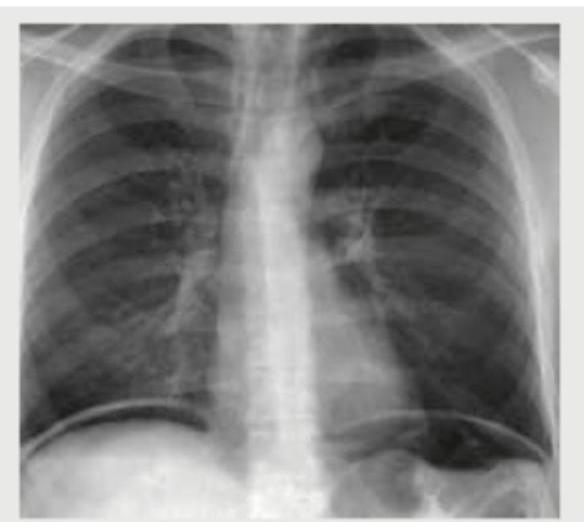

Question 5: An adult undergoes multiple FFP transfusions for excessive bleeding after cardiac surgery and develops respiratory distress. CXR done is shown below. What does it indicate?

- D. TRALI (Correct Answer)

Explanation: ***TRALI*** - The chest X-ray shows **bilateral pulmonary infiltrates** and **pulmonary edema** and the patient had multiple **FFP transfusions** followed by respiratory distress, which is highly suggestive of **Transfusion-Related Acute Lung Injury (TRALI)**. - TRALI is characterized by acute respiratory distress with **hypoxemia** occurring within 6 hours of transfusion, in the absence of other risk factors for **Acute Lung Injury (ALI)**. *Volume overloading of heart* - While fluid overload can cause pulmonary edema, the severity and rapid onset of distress after transfusion, coupled with the bilateral infiltrates, point more specifically to TRALI rather than isolated volume overload, especially in the context of FFP. - Cardiogenic pulmonary edema typically presents with **cardiomegaly** and signs of **heart failure**, which are not explicitly described or obviously seen as the primary cause in the given scenario and image. *Mendelson's syndrome* - Mendelson's syndrome, or **aspiration pneumonitis**, results from the inhalation of acidic gastric contents, leading to chemical pneumonitis. - This typically occurs in patients with impaired consciousness or those undergoing procedures that compromise airway protection, and there is no information in the vignette to suggest aspiration. *Pneumomediastinum* - Pneumomediastinum indicates the presence of **air in the mediastinum**, which would appear as radiolucent streaks outlining mediastinal structures on a CXR. - The image primarily shows diffuse bilateral infiltrates and pulmonary edema, rather than free air in the mediastinum.